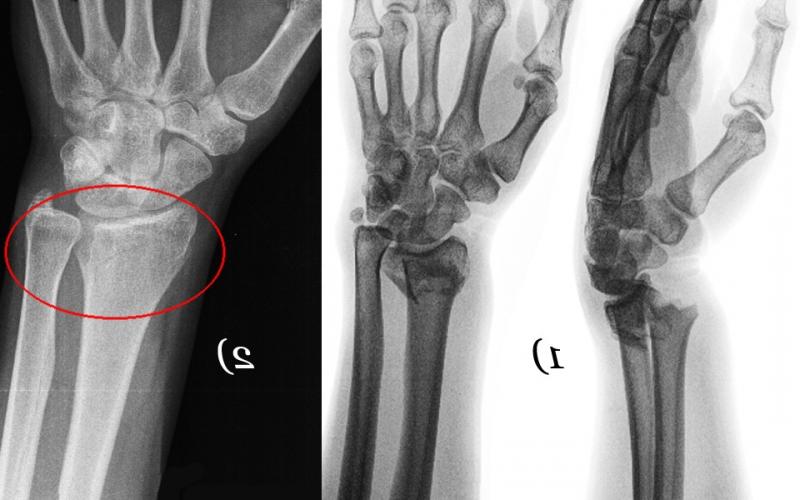

Поставить диагноз по одной клинической картине невозможно. Для этого врачам необходимо обнаружить признаки вывиха руки на рентгенограмме. Во время обследования специалисты выявляют у больного смещение одной или нескольких костей запястья.

После подтверждения диагноза врачи определяются с лечебной тактикой. Чаще всего они выполняют закрытое вправление с дальнейшей фиксацией кисти гипсовой лонгетой. Спустя 4 недели гипс снимают и оценивают состояние лучезапястного сустава. При наличии нестабильности хирурги выполняют фиксацию спицами Киршнера.